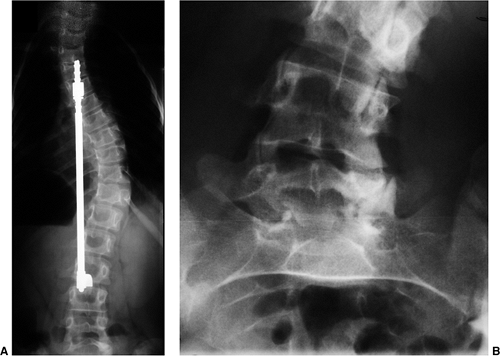

Figure 18.11 A:

This 10-year-old girl presented with symptoms of increasing trunk decompensation, as well as low back pain and posterior thigh discomfort. She has an obvious trunk shift to the left, suggesting scoliosis. The posteroanterior rather than anteroposterior view is preferred because there is reduced radiation exposure. B: The standing-position posteroanterior radiograph confirms a 43-degree left lumbar scoliosis. C: Standing-position lateral view focused at the L5-S1 level demonstrates severe spondylolisthesis. Most of this patient’s lumbar deformity is related to an asymmetric forward slipping of L5 on S1, with rotational deformity translated to the lumbar spine above. Following correction of her spondylolisthesis with fusion from L4 to the sacrum, her scoliosis reduced to less than 15 degrees.  |